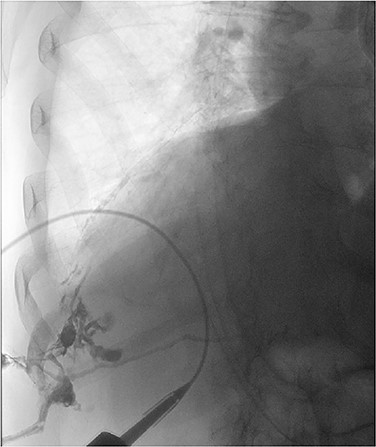

The patient recovered well, but <1 month later he noticed an additional draining sinus at the right flank. A fistulogram (Fig. 1) was performed, and it showed a connection between the sinus and a right lower lobe bronchiole. He was taken to the OR for a right thoracotomy with wedge resection of the right lower lobe of the lung and excision of a broncho-pleuro-cutaneous fistula that was found to contain pieces of golden pigmented solid material, which was concluded to be consistent with a gallstone (Fig. 2). This case report presents a patient with an uncommon complication from a dropped gallstone: a broncho-pleuro-cutaneous fistula.

Contrast study of the broncho-pleuro-cutaneous fistula formed by the dropped gallstone